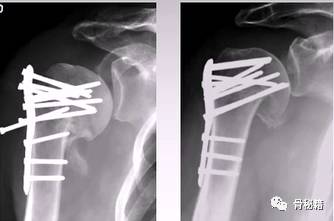

病例1

4部分骨折

正位的翘拨复位

腋位的翘拨复位

解剖钢板与提拉螺钉的复位

需要注意 不要应用过度提拉 使得内侧肱骨距过复位

注意完成内侧支撑和内外翻的复位

在此病例中,为了复位良好,舍弃了肱骨近端与钢板贴服